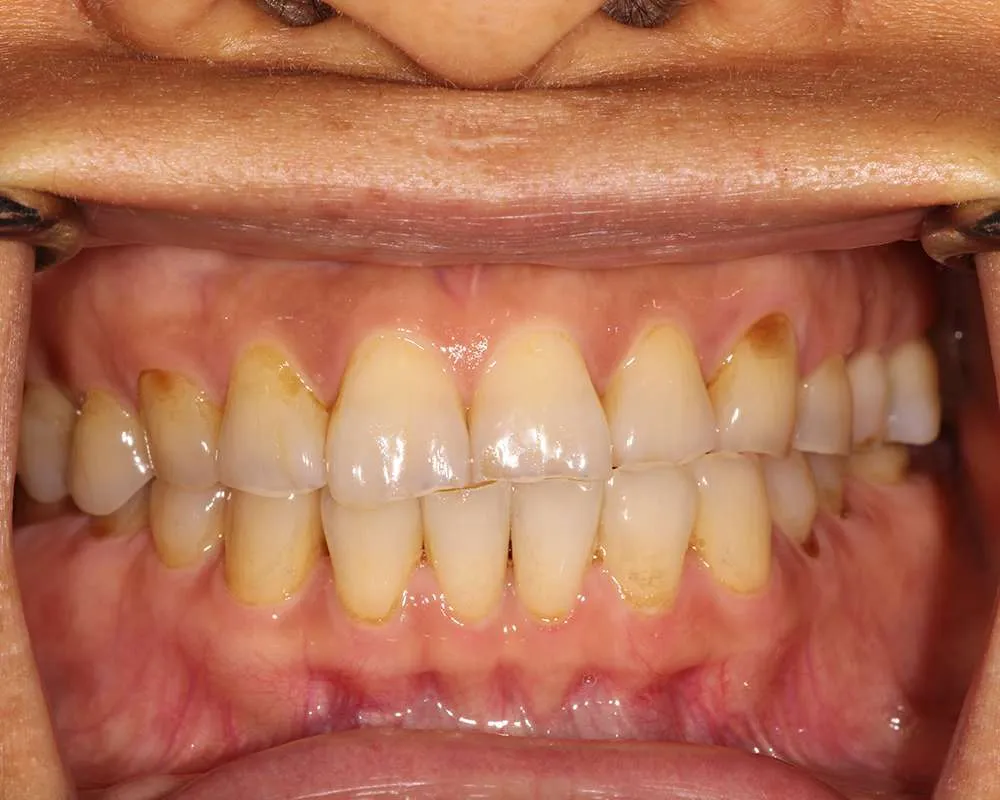

Real Stories, Real Results: Case Studies Showcasing How Our Personalized Approach Transforms Smiles and Lives

Complex Cases

Witness the Remarkable Changes We Can Achieve